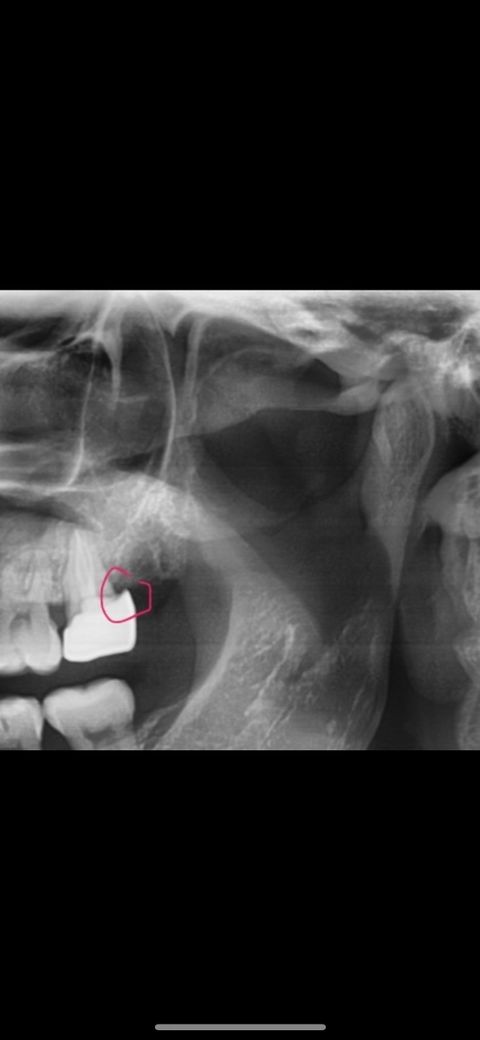

크라운 최종 부착 했는데 다른병원가서 엑스레이 찍었더니 크라운에 틈이 있다네요?? 그리고 접착제도 제대로 제거 안해놔서 다른병원에서 긁어주셨구요

마진도 이상한거죠??

경계 부위 적합도가 떨어지는 것으로 보이지만 부착당시 잇몸 상태 등 고려해야할 것들이 많습니다.

사진으로 봤을 경우에는 경계부위가 떠있는것으로 보입니다.

잇몸에 출혈이 많거나 접근도가 좋지 않은 경우 경계부위가 적합이 되지 않을수도 있습니다.

경계부위의 적합이 잘 되지 않으면 나중에 해당부위에 음식물이 끼게 되어 충치가 진행될수 있기 때문에 보철물을 다시 제작해 주는것이 좋습니다.